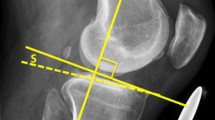

The utility of lateral radiographs of the knee cannot be overstated as well in order to both assess the patient’s native tibial slope and plan an osteotomy that appropriately alters the native sagittal plane anatomy. Multiple methods for measuring the native slope of the tibia have been described and used reliably (Fig. 2), although it has been shown that the anterior tibial cortex (ATC) measurement method may overestimate tibial slope, while the posterior fibular anatomic axis (PFAA) method may underestimate tibial slope [61]. Still, there is no consensus about which method should be used; no method has been shown to be most accurate.